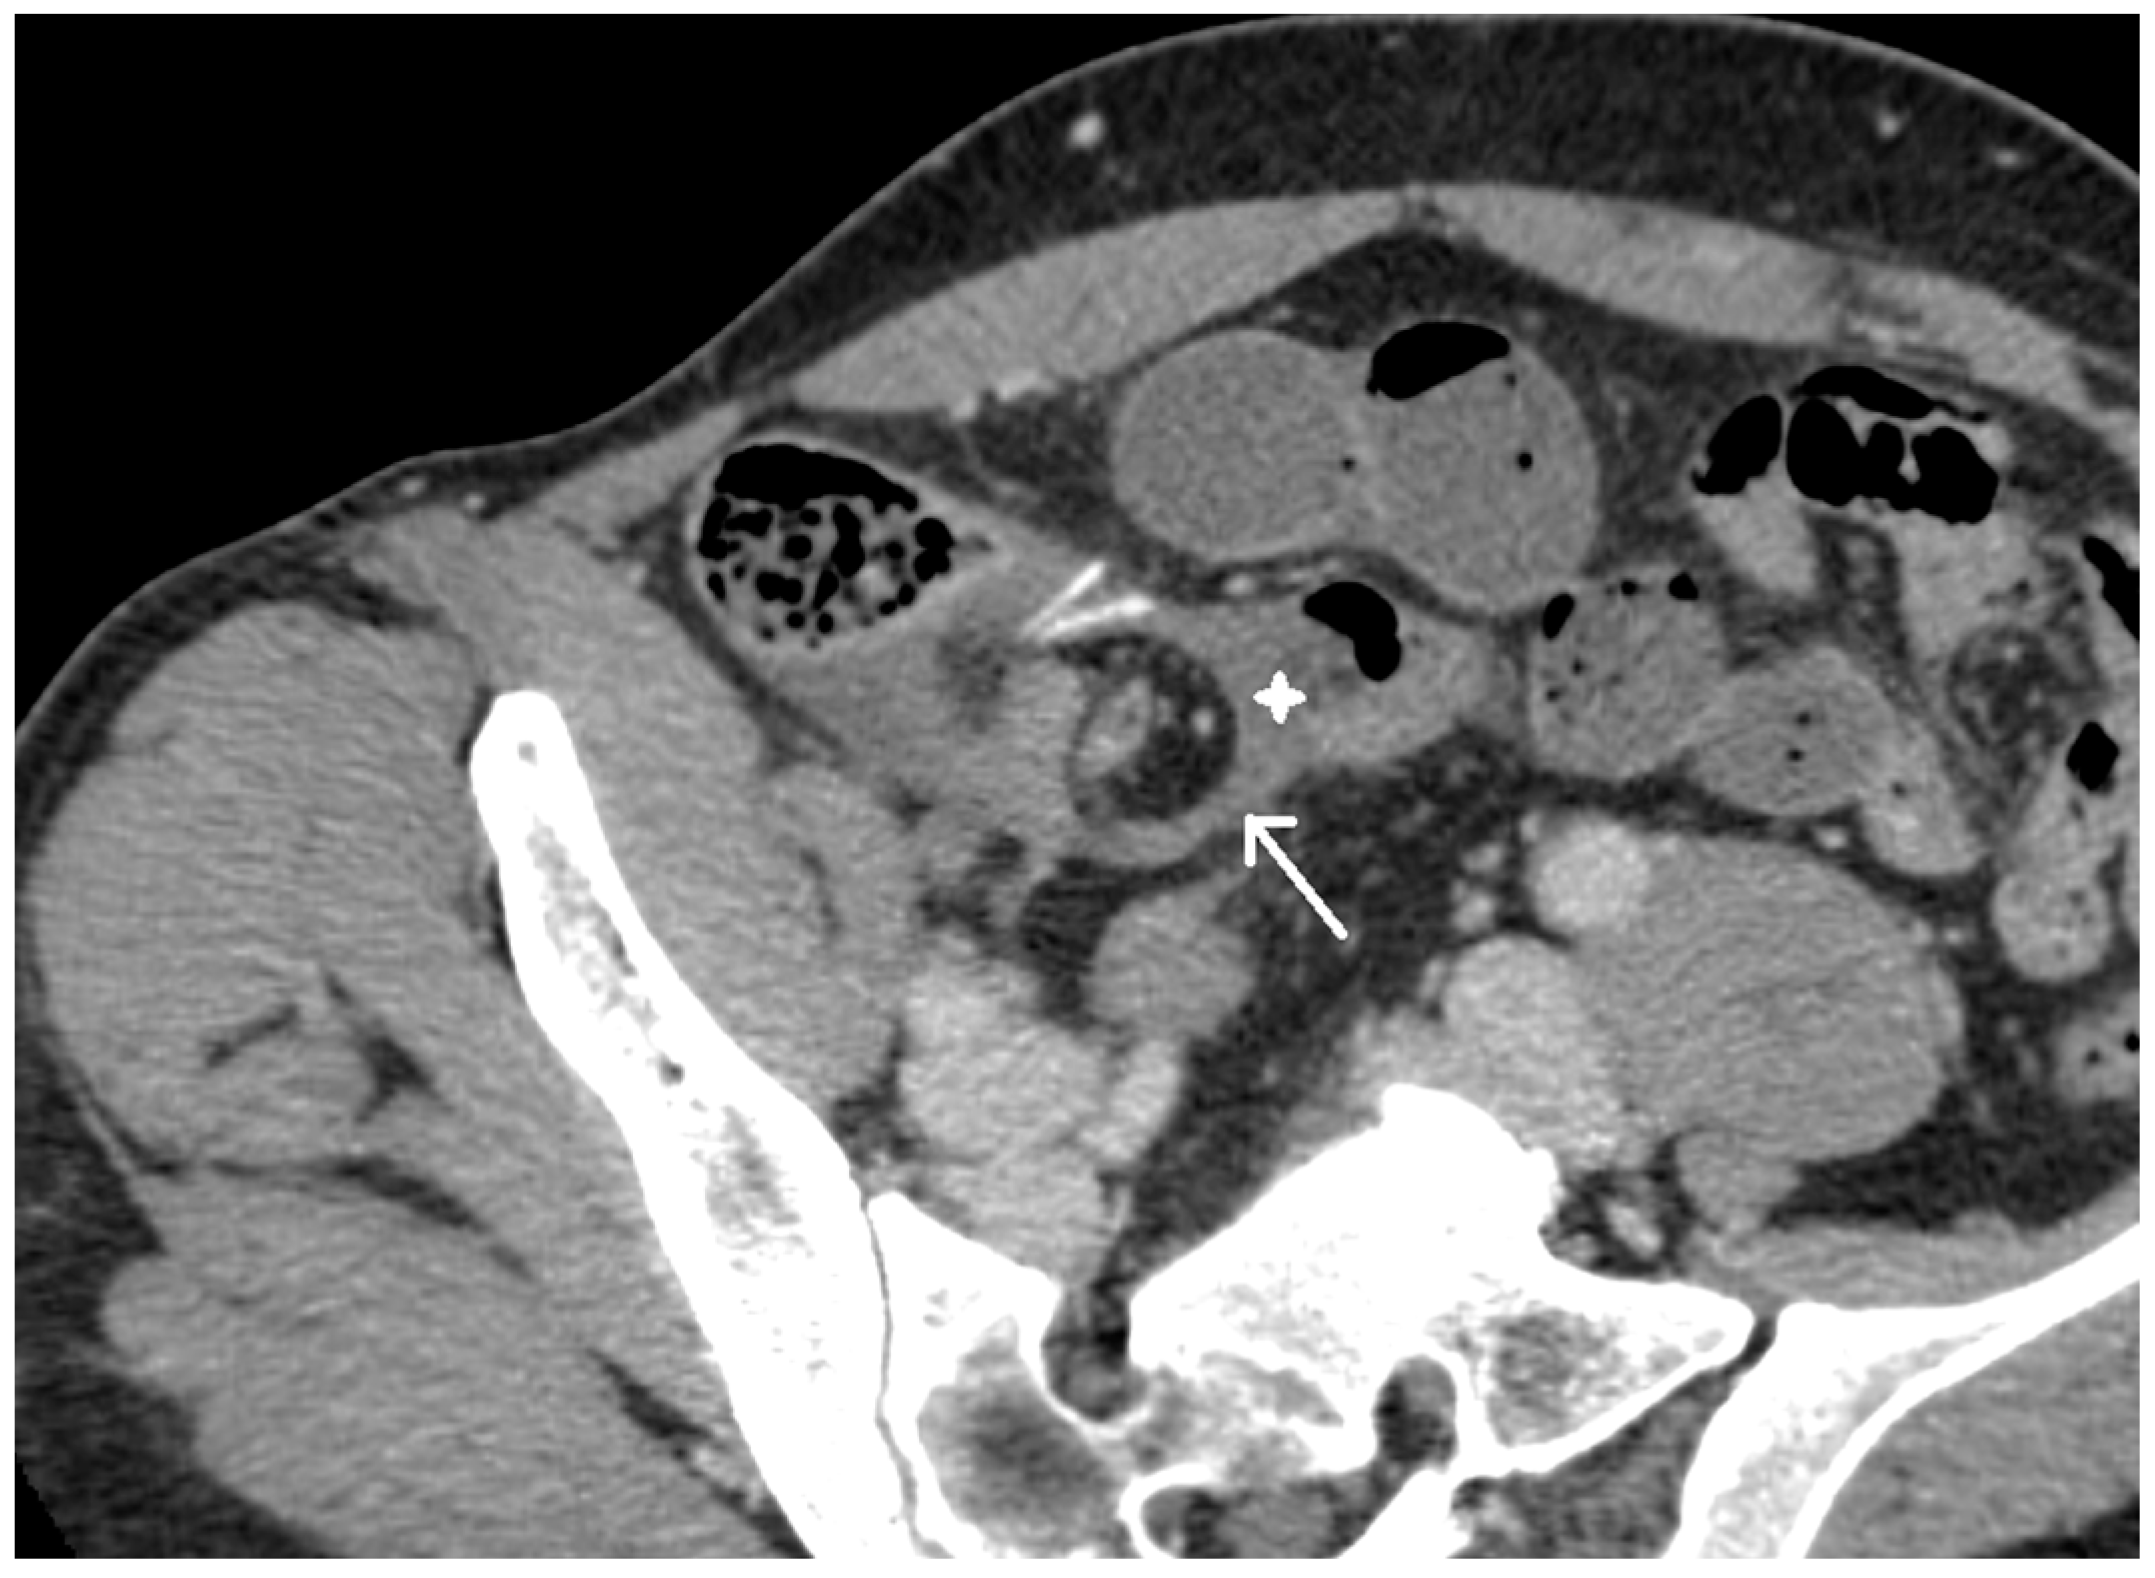

2. Case Presentation